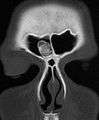

An osteoma (plural: "osteomata") is a new piece of bone usually growing on another piece of bone, typically the skull. It is a benign tumor.

Osteoma represents the most common benign neoplasm of the nose and paranasal sinuses. The cause of osteomata is uncertain, but commonly accepted theories propose embryologic, traumatic, or infectious causes. Osteomata are also found in Gardner's syndrome. Larger craniofacial osteomata may cause facial pain, headache, and infection due to obstructed nasofrontal ducts. Often, craniofacial osteoma presents itself through ocular signs and symptoms (such as proptosis).[1]